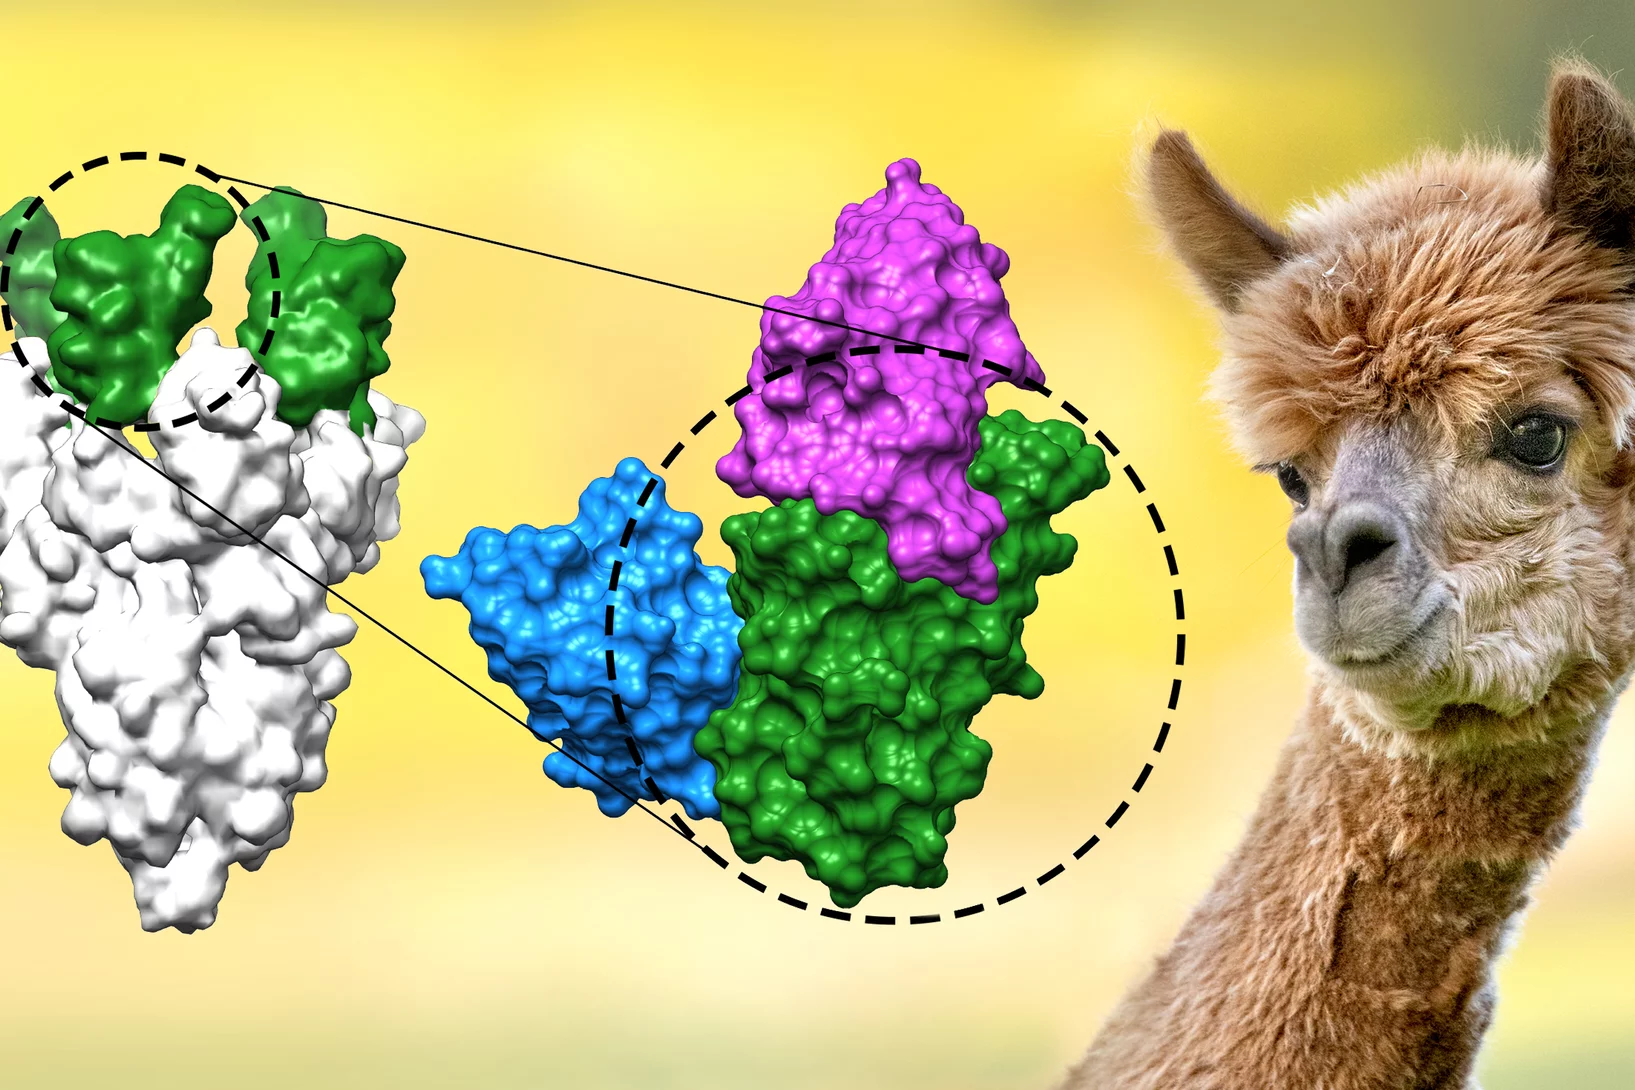

Nanobodies against SARS-CoV-2

In a study published in EMBO Journal, researchers at the Max Planck Institute for Biophysical Chemistry, Göttingen, Germany, developed nanobodies that efficiently block the coronavirus SARS-CoV-2 and its variants. The high resolution structural characterization was performed at the X10SA crystallography beamline at the Swiss Light Source.